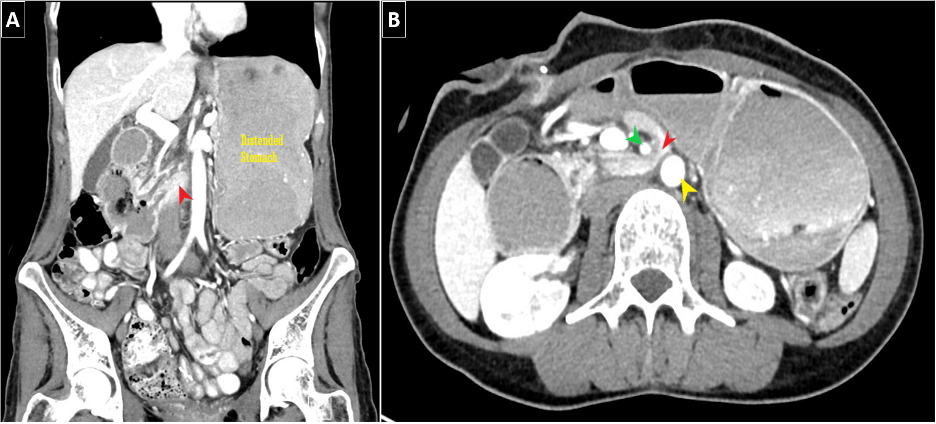

A diagnosis of SMAS consists of both clinical symptomatology and associated imaging findings of duodenal obstruction. Multiple modalities can be utilized to assess for SMAS (e.g., CT, US, MRI, EUS); however, the most beneficial modality would be CT imaging as it can not only confirm SMAS in multiple views (Figure 1), but also provide supporting data such as SMA-AA angle/distance and/or identify the aforementioned complications of SMAS. On CT imaging, the standard SMA-AA angle, distance typically ranges from 38-65 degrees and 10-33 mm, respectively (1,3). Unal et al (2005) determined that the cutoff values of 22 degrees (SMA-AA angle) and 8 mm (SMA-AA distance) for SMAS had 42.8% sensitivity/ 100% specificity and 100% sensitivity/100% specificity–respectively. Abdominal US has been shown to be an effective modality in diagnosing SMAS. In recent literature, the use of EUS has become more commonplace as it can not only confirm duodenal compression but also now measure both SMA-AA angle and distance (1).

It is worthwhile to mention that SMAS can, at times, present alongside additional vascular compression syndromes. Most commonly, this being nutcracker syndrome (left renal vein compression between the SMA and AA) based on the anatomical location (Figure 2). Another example would be celiac axis compression syndrome which occurs due to compression of the celiac artery by the median arcuate ligament (1).